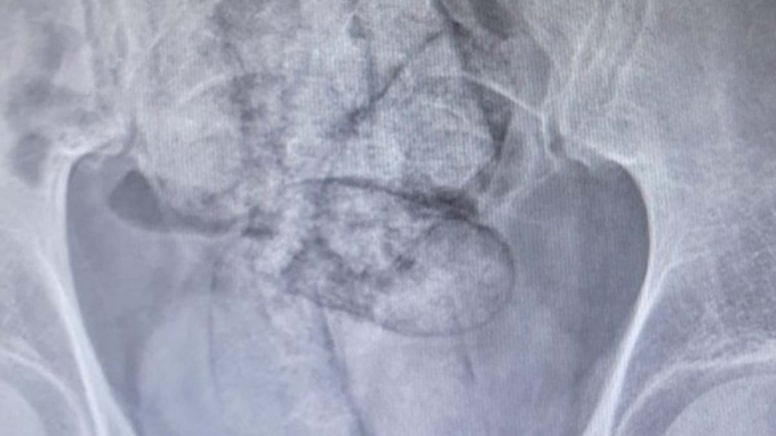

Üst aramasında uyuşturucu madde bulunamayan şüphelinin, Artvin Devlet Hastanesi’nde tomografi ile yapılan incelemede karın ve bağırsak bölgesinde yabancı cisim olduğu tespit edildi.

Bağırsak tıkanıklığı yaşayan ve hayati tehlikesi bulunması nedeniyle ameliyata alınan şüphelinin bağırsaklarından 10 paket halinde 350 gram metamfetamin ele geçirildi.